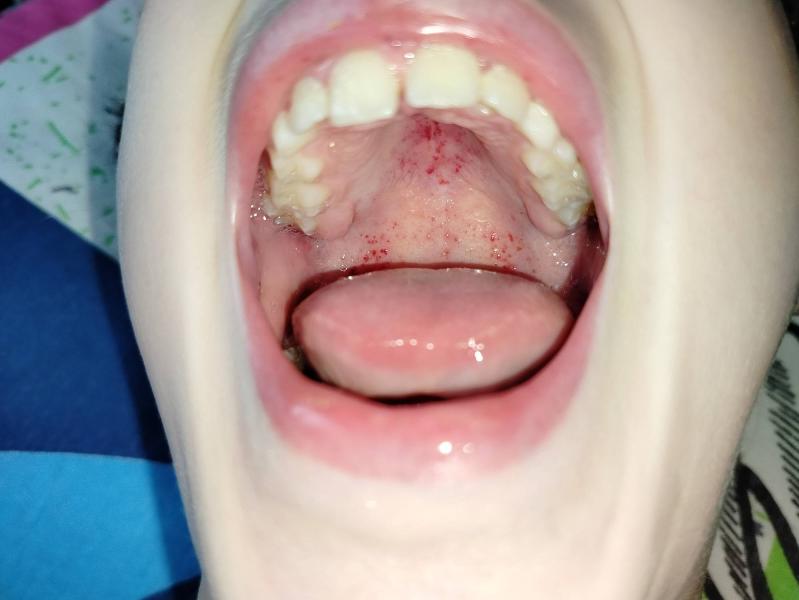

Сегодня сыпь и сильная боль в горле, есть ничего не может (все зипит и раздражает).

Меня больше беспокоит сыпь. Никогда ничего похожего не было

А на ступнях и ладонях была? Сыпь выпуклая?